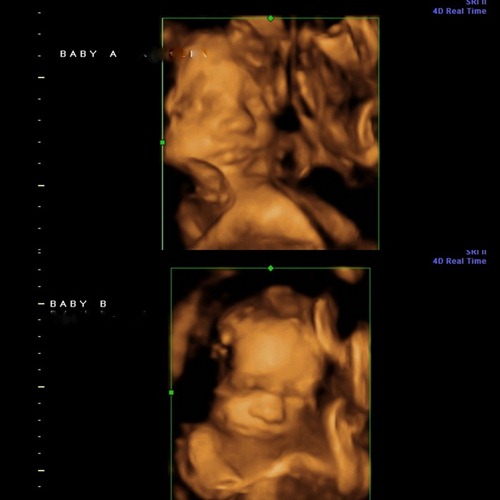

First things first, I thought Iβd give you an update on the twins.

I had my second sonogram on Monday (when you use a midwife, you donβt usually have but one, but since itβs twins, we wanted to see how the girls were faring firsthand).

It was such a treat to get to see my babiesβ precious faces.

As long as there truly is only one placenta in there, then the likelihood of their sharing the same DNA and thus being identical is almost 100%, but thereβs always a chance that thereβs something they canβt quite see exactly right, so Iβm actually really looking forward to seeing how similar they look when they decide to make their grand entrance.

I will say, though, that from the 3D sono alone, they look very much alikeβsame noses, same adorable poochy bottom lips (they actually look a lot like Dellaβs 3D sono picturesβ¦watch out, World!).

Oh, andβPraise Jesus!βthey are doing absolutely awesome.

They each weigh more than the average singleton at 29 weeks (the sono tech could see fat rolls on their little bottoms!) and are measuring exactly as they should, which is such a huge relief since the number one concern for twins that share the same placenta is TTTS, which occurs when one twin gets a larger share of nutrients/blood from the cord and ends up weighing considerably more than the other.